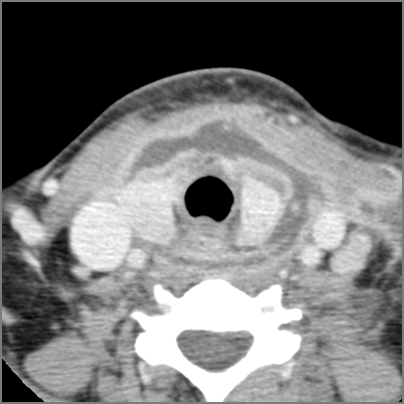

9 month old male presenting to the emergency room with poor feeding, fever, respiratory distress and possible retropharyngeal abscess or suppurative retropharyngeal adenitis.Exam

| Retropharyngeal Lymph Nodes | Correct Answer | Your Answer |

|---|---|---|

There is reactive retropharyngeal lymphadenopathy. |

Yes | NA |

There is suppurative retropharyngeal lymphadenopathy. |

If there is suppurative retropharyngeal adenopathy what is the maximum short axis dimension of the largest suppurative node. Measurement |

< 2cm | NA |

There is edema/abscess within the adjacent parapharyngeal and retropharyngeal spaces. |

Impression

Expert Answer

Pharyngitis with suppurative retropharyngeal adenitis.